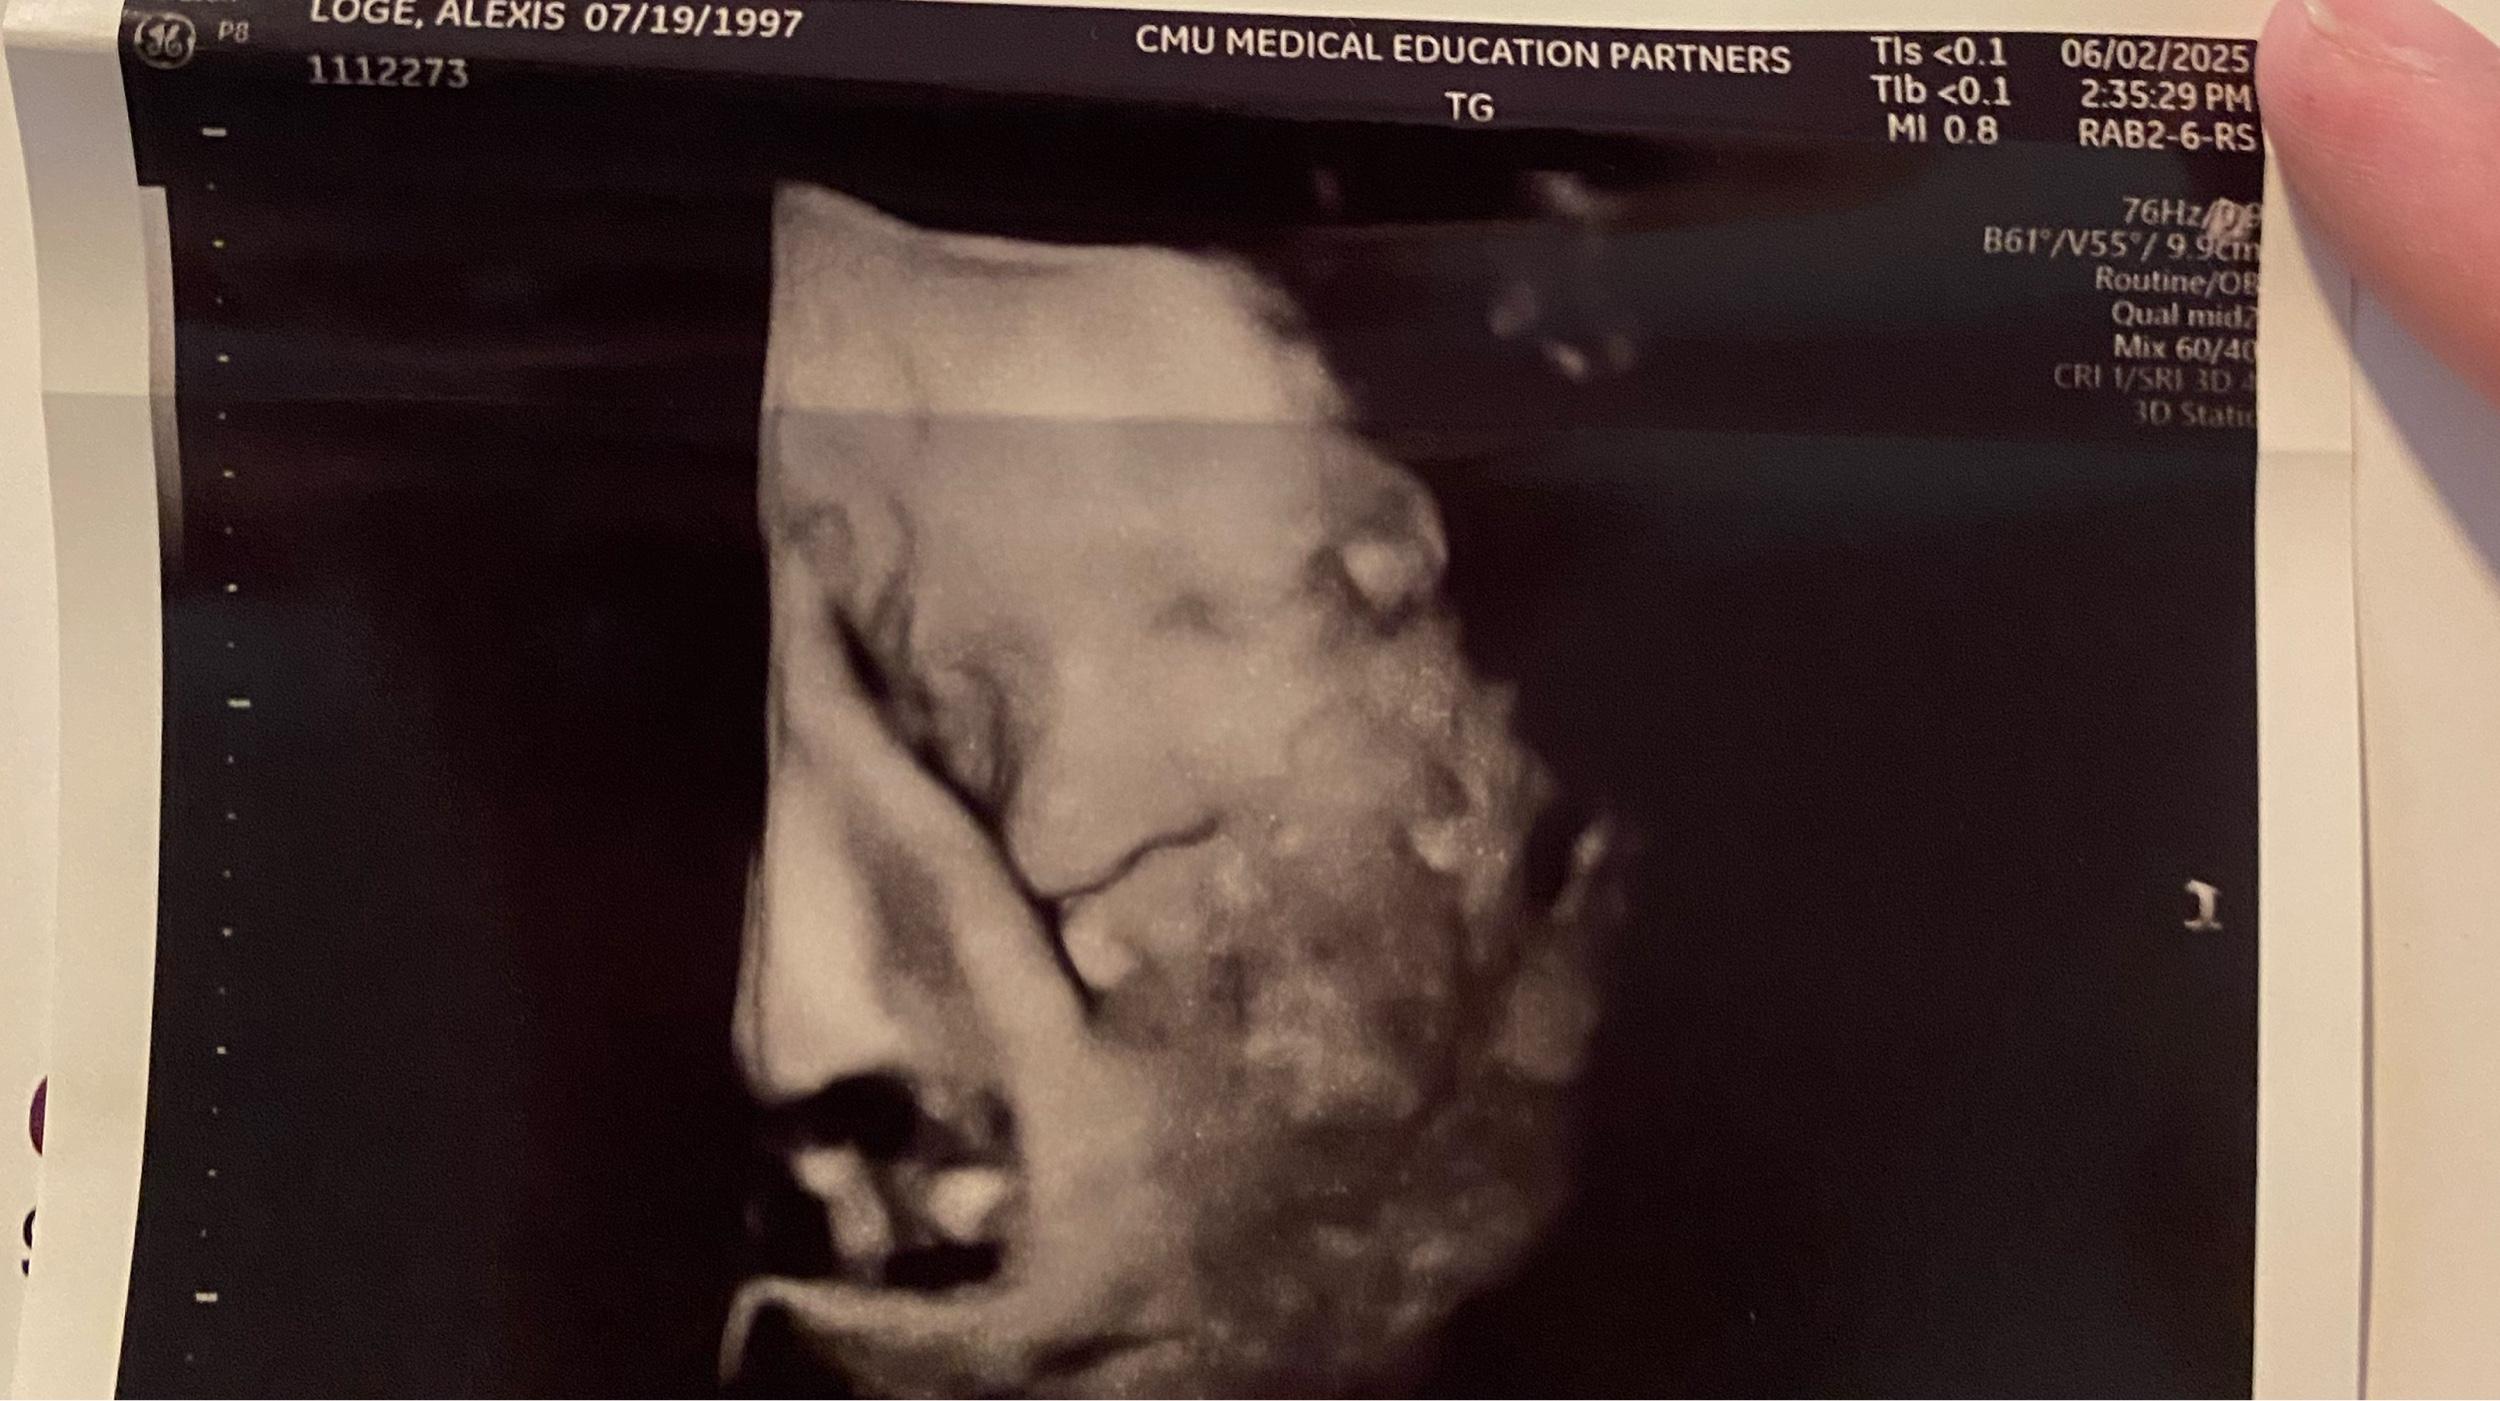

Baby Daniel

Arrival date June 28, 2025